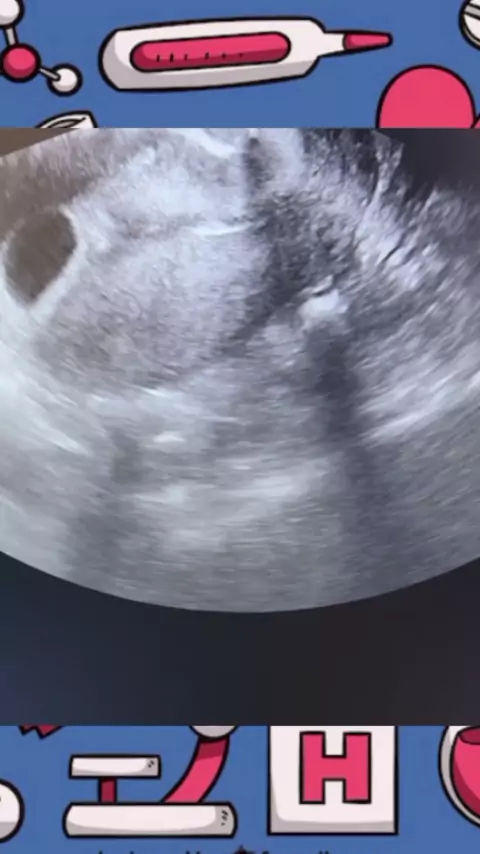

Saúde Medicina e Partos

#saude #medicina